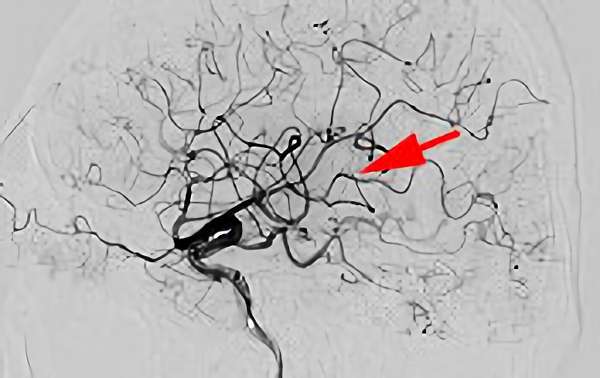

'26年3月

出血性脳動静脈奇形

10代

院内外来

No.1620 手術前

No.1620 手術中

No.1620 手術後